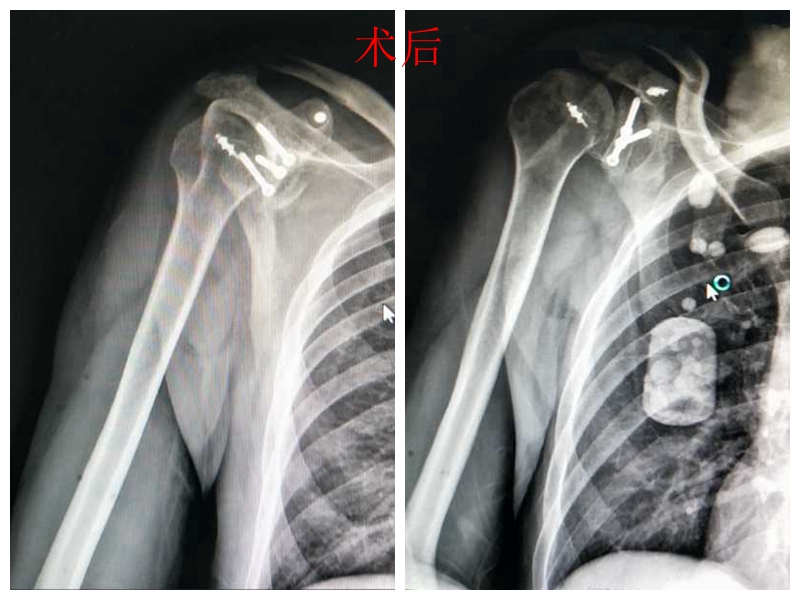

接诊后,肩肘手足科主任、主任医师王胜冬,带领科室人员仔细阅片,认为其肩关节陈旧性、复发性脱位时次数频繁,已经造成了右肱骨头、肩胛盂、喙突陈旧性骨折和右肩袖缺损,关节越来越不稳定,传统手法复位,收效甚微。为彻底解决复发这一棘手的问题,经会诊讨论,决定为其施行右肩关节陈旧性复发性脱位并肩关节周围陈旧性骨折、肩袖损伤切开复位、粘连松解、肱骨缺损修复、肩袖修复、关节盂修复、植骨内固定术。但邓先生患有胰腺炎、糖尿病、酒精性肝病、酒精性胃病,基础疾病多,麻醉、手术风险大,专家团队制定了详细的手术方案和术后康复计划。

邓先生受伤后,肱骨头骨折损伤、肩胛盂损伤是肩关节不稳定的重要因素,术中的难点在关节粘连的松解复位,肱骨头缺损的修复、关节盂的修复,植骨选择。术中,以王胜冬主任为首的专业团队,通过小切口,将肩胛骨上带肌腱的喙突骨块,移位到肩关节前下方,形成一个坚强的动力性骨性支柱,肱骨头缺损用岗下肌填塞,防止肱骨头外展外旋时反复脱位,实现了精准牢固的治疗。

术后,经过康复训练,邓先生终于摆脱了“肩关节陈旧性复发性脱位”这一纠缠他1年多的“梗”,目前,他的基本生活功能恢复,屈伸程度良好,顺利出院。